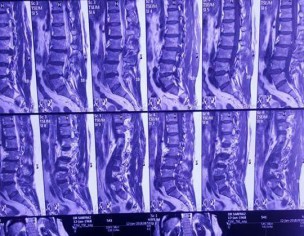

Lower back pain couple of years. Pain right thigh right knee joint. No recent trauma.

Thank you Dr sarfraz for asking. Although the radiographs and MRI are showing degenerative changes of spine and disc bulge as well, but a clinical examination is required. Cauda equina syndrome, characterized by loss of bladder or bowel function and saddle Anesthesia warrants emergency surgery. All other procedures are elective, depending on the clinical significant finding.

mri shows L3/4 disc prolapse.